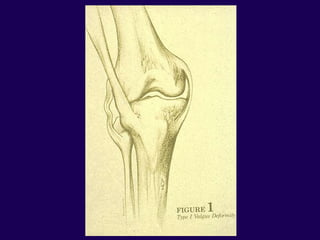

Surgical Techniques

Valgus Knee

1. Iliotibial Band

2. Popliteus Tendon

3. Posterior Lateral Capsule

4. Lateral Head of Gastroc

5. Biceps Femoris